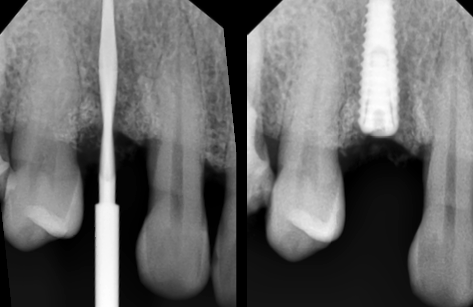

Apariția implanturilor dentare a dus la scăderea numărului de lucrări protetice mobilizabile (lucrări care se îndepărtează). După pierderea unui dinte se examinează vo lumul osos remanent, iar dacă osul este suficient se inseră implantul dentar, care este practic un înlocuitor pentru rădăcină (Fig. 3.5.1 și Fig. 3.5.2). Se așteaptă vindecarea pe o perioadă cuprinsă între 3 și 6 luni (Fig. 3.5.3). Se verifică radiografic poziționarea corectă a implantului (Fig. 3.5.4).